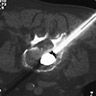

Θεραπεία της ασβεστοποιού τενοντίτιδος του ώμου (Barbotage)

Τεχνική:

Κάτω από τον έλεγχο των υπερήχων η της αξονικής τομογραφίας εντοπίζεται η ε

Κάτω από τον έλεγχο των υπερήχων η της αξονικής τομογραφίας εντοπίζεται η επασβέστωσ